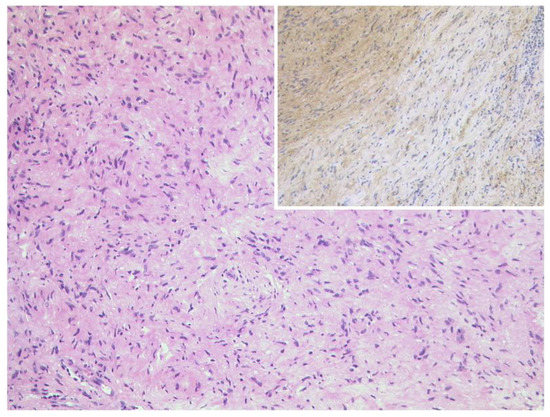

3.5.1. Schwannoma

3.5.2. Neurofibroma